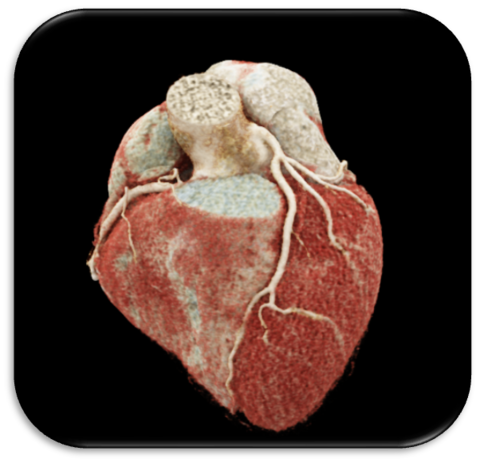

mit der kardiovaskulären Ambulanz RADIANZ bieten wir Ihnen eine unkomplizierte Möglichkeit, kardiale Erkrankungen wie z.B. die koronare Herzerkrankung mittels non-invasiver Bildgebung ambulant abzuklären - Leitlinienkonform und mit dem Ziel des sicheren Ausschlusses einer relevanten koronaren Gefäßverengung. Dies ist möglich bei symptomatischen Patienten mit dem chronischen Koronarsyndrom (CCS) oder vor einer großen Operation - wir prüfen gern die Indikation auf Ihrer Überweisung.

Als RADIANZ-Patient:in organisieren wir die Untersuchung und Sie erhalten einen Termin zur Befundbesprechung und Erklärung der Bilddaten, vor Ort oder per Video-Call. Insbesondere die Plaqueanalyse in den Koronargefäßen liegt uns am Herzen. Diese sogenannten Bild-Biomarker sind ultimativ wichtig für Ihre persönliche Prognose. Gerne nehmen wir auf Wunsch auch Kontakt mit Ihren Ärzt:innen auf.

Unsere Ambulanz bündelt das gesamte Spektrum der modernen non-invasiven Herzbildgebung:

- Koronar-CT und Klappen-CT inklusive präinterventioneller Planung,